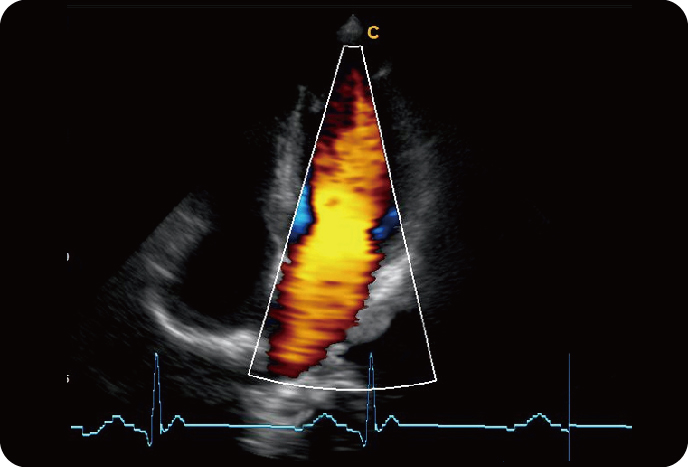

Секторный Фазированный